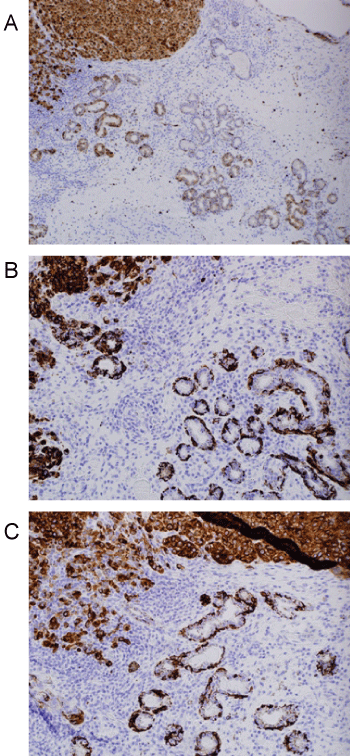

Histologic evaluation disclosed a pigmented focally ulcerated mass surrounded by a zone of pigmentation within both the mucosa and some of the seromucinous glands. The mass was composed of atypical oval to polygonal cells with scant to modest amounts of cytoplasm containing scattered brown pigment. Morphologically, the neoplasm was consistent with malignant melanoma (Figure 2A and Figure 2B). No in-situ component of the melanoma was seen. The mucosa over the mass was ulcerated and the neoplastic cells invaded the underlying soft tissues and surrounded and destroyed the entrapped seromucinous glands. At the periphery of the mass, the seromucinous glands contained pigment morphologically identical to that seen in the melanoma (Figure 3A). The pigment lay in the cuboidal to low column cells lining the lumen of the glands (Figure 3B). Immunohistochemical staining for S-100 protein, HMB-45 and melan A showed the glandular cells to be immunoreactive for these three antigens (Figure 4A, Figure 4B and Figure 4C). The cuboidal cells also contained granular pigment positive by the Fontana-Masson reaction. This black pigment was most intense near the laminal surface of the cells (Figure 5). Occasional Fontana-Masson positive cells were present in the overlying mucosa near the melanoma and occasionally loose in the stroma (Figure 6).

Figure 2: A) Photomicrograph of mass lesion composed of atypical oral and polygonal cells representing malignant melanoma (H+E, X200); B) The oval and polygonal cells demonstrate nuclear hyperchromasia and membrane irregularities (H+E, X400). View Figure 2

Figure 4: A) S100 stain demonstrating positivity in melanoma and adjacent glands (Immunohistochemistry, X100); B) HMB45 staining in both glandular epithelium and adjacent melanoma (Immunohistochemistry, X200); C) Reactivity for melan A in both melanoma and glands (Immunohistochemistry, X200). View Figure 4